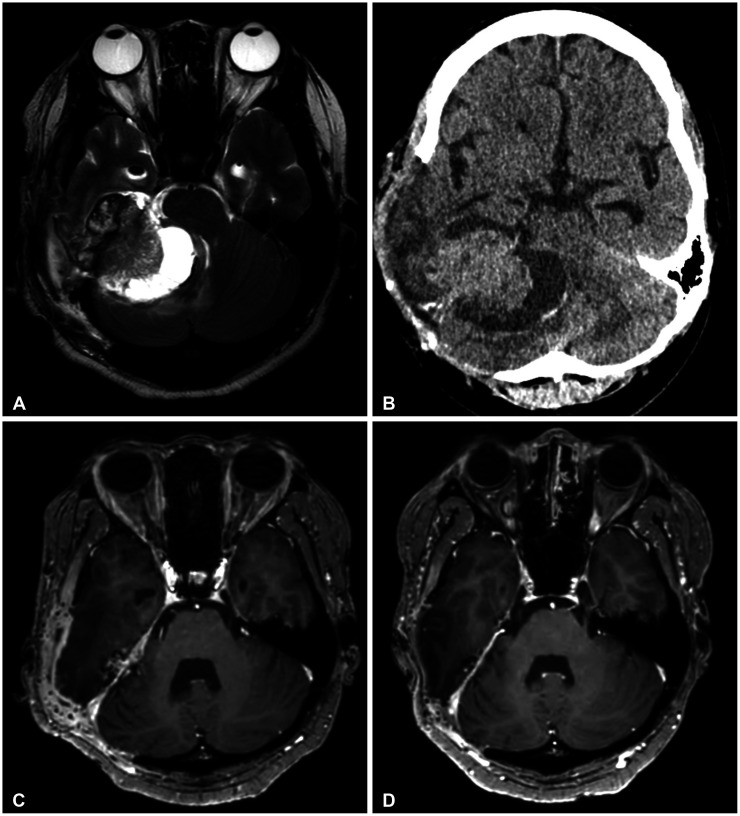

Ewing sarcoma and peripheral primitive neuroectodermal tumor (ES/pPNET) is an undifferentiated malignant tumor that is most prevalent in children and young adults and often radiologically mimics a meningioma. A 38-year-old female patient visited our hospital with complaints of right-sided tinnitus, right hemiparesis, and imbalance. She underwent preoperative imaging and was subsequently diagnosed as having a meningioma on the petrous ridge. After partial resection, EWSR1-FLI1 gene fusion was confirmed, and she was diagnosed with ES/pPNET. The tumor was successfully treated using a multidisciplinary approach of adjuvant chemo- and radiotherapy. This case is noteworthy because it is an extremely rare case of an intracranial ES/pPNET, and it is worth sharing our clinical experience that the tumor was successfully treated through a multidisciplinary therapeutic approach even though complete resection was not achieved.